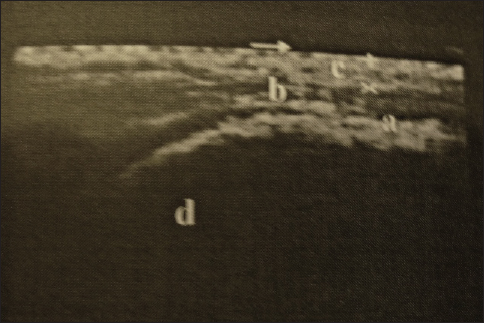

Diagnostic imaging by radiographic examination was limited to identifying overriding thoracic dorsal vertebral spinous processes using an output of 20 mA at 90 kV within 0.1 second. However, most projections suffer from superimposition of the lungs and poor resolution. Ultrasonographic examination of the thoracolumbar dorsal spines and sacroiliac region revealed 30 cases with sacroiliac pain or injuries with heterogenic echogenicity and thickening of the dorsal sacroiliac ligament, 16 cases with dorsal spinous desmopathy, and 8 cases with echogenic changes of longissimus dorsi aponeurosis (Fig. 5).

Fig. 5. Longitudinal ultrasonography of the sacroiliac region showing sacroiliac desmopathy (a-sacroiliac enthesophytosis, b-longissimus dorsi tendon, c-gluteal fascia, and d-sacral tuber).